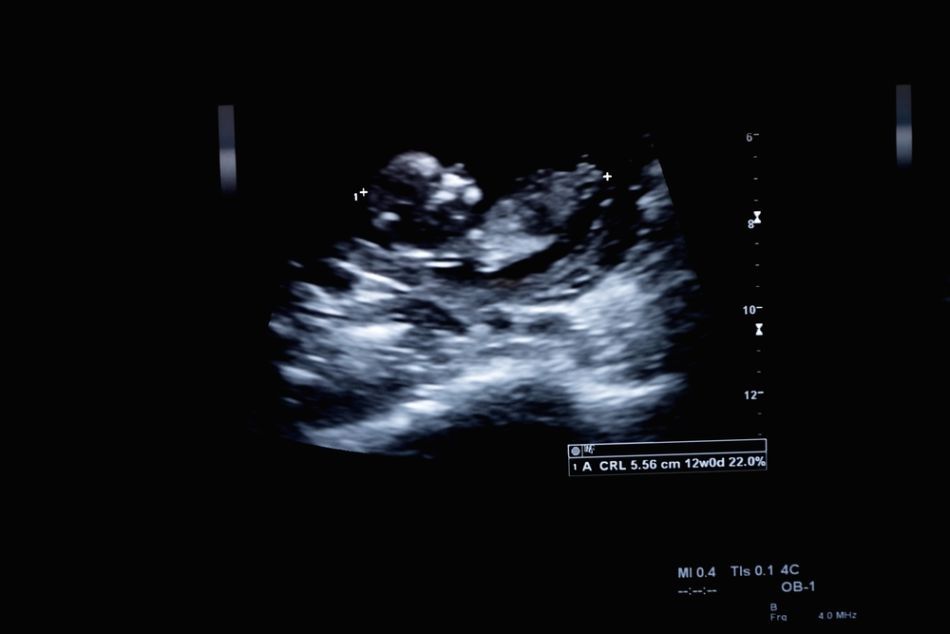

Ecografia unui fetus uman de trei luni de zile.    sursa foto: ShutterstockEcografia unui fetus uman de trei luni de zile.